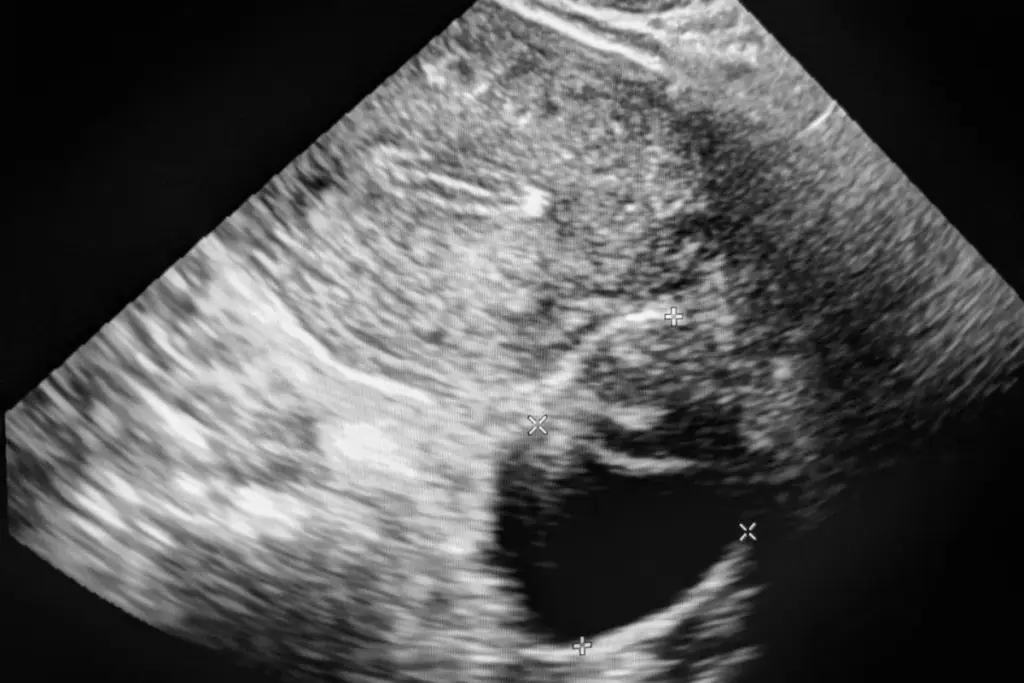

Detecting Testicular Cancer on Ultrasound

Ultrasound helps find testicular cancer by looking closely at the testicles for any oddities. This method is safe and lets doctors see inside the testicles. It’s key for spotting tumors or lumps.

Appearance of Tumors

Ultrasound can show testicular cancer as a lump or mass. These tumors might look different from the rest of the testicle. They often change the normal echo pattern of the testis. Doctors look for any unusual spots or tiny stones that could mean cancer.

Not every lump or nodule is cancer. But, any odd growth needs to be checked out. How a tumor looks on ultrasound helps decide what to do next.

Distinguishing Between Benign and Malignant Growths

Telling if a growth is harmless or cancerous is key. Ultrasound gives clues, but doctors also use other tools and check the patient’s history. They look at the size, where it is, and how it looks on ultrasound, along with the patient’s symptoms and past health.

Doctors use ultrasound and other checks to make a good diagnosis. Knowing how testicular cancer looks on ultrasound is important. It helps find cancer early and treat it well.

What does testicular cancer look like on an ultrasound?

On ultrasound, testicular cancer shows up as a darker area in the testicle. This area might be well-defined or irregular. It could have a “microlithiasis” pattern.